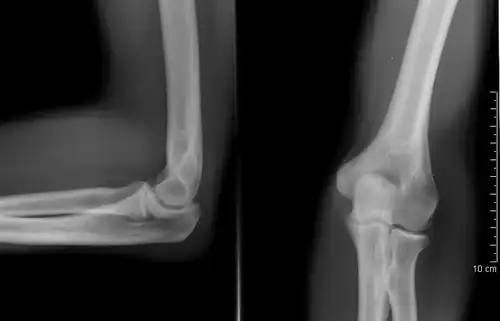

Left: Lateral X ray of a dislocated right elbow

Right: AP X ray of a dislocated right elbow